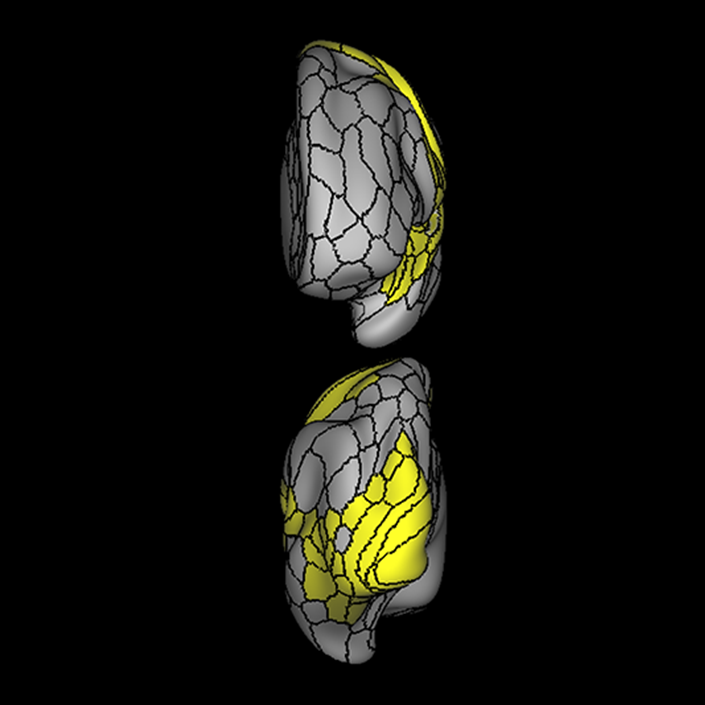

ᐅ SummaryArea 44: part of the inferior frontal gyrus of the lateral frontal lobe. Translates abstract and intentional information in the prefrontal cortex to more detailed representations to help guide the production of verbal and manual actions. In addition to its known association with Broca's area, is sometimes represented as part of Broca's complex ᐅ Where is it?Area 44 is at the posterior most part of the inferior frontal gyrus. It is the anterior bank of pars opercularis of the IFG. ᐅ What are its borders?Area 44 borders area 45 anteriorly and area 6r posteriorly. Area 8C is its medial border and its inferior border is wedged between then upper borders of Areas 6R and 6V. Its superior edge borders IFSp and IFJa. Its opercular surface is FOP4. ᐅ What are its functional connections?Area 44 demonstrates functional connectivity to areas SFL, IFSp, IFJa, 45, 47s, 47L, 9a, 9m, 8AV, 8BL and 8C in the dorsolateral frontal lobe, area 8BM in the medial frontal lobe, area 55b in the premotor areas, areas FOP5, AVI and PSL in the insula- opercular region, areas TGd, STSdp and STSvp in the temporal lobe, areas PFm, and PGi in the inferior parietal lobe, and no areas in the medial parietal lobe. ᐅ What are its white matter connections?Area 44 is structurally connected to the arcuate/SLF and the FAT. Connections with the arcuate/SLF project posteriorly and wrap around the Sylvian fissure to the middle temporal gyrus to end at TE1a and TE1m. There are also projections from the arcuate/SLF before it terminates to parcellations A5 and STSdp. The majority of the inferior connections of the frontal aslant tract end at 44, the tract is connected superiorly to superior frontal gyrus parcellations SFL, 6ma and s6-8. Local short association bundles are connected with 45 and 8C. White matter tracts from 44 in the right hemisphere have less consistent connections with the arcuate/SLF. ᐅ What is known about its function?Area 44 translates abstract and intentional information in the prefrontal cortex to more detailed representations to help guide the production of verbal and manual actions. Area 44, in addition to its known association with Broca's area, is sometimes represented as part of "Broca's complex", including Brodmann Areas 45, 46, 47 and the mesial supplementary motor area of 6, which contribute to a frontal-subcortical circuit. The right pars opercularis has also been implicated in cognitive inhibition in the overall context of working memory. |

A: lateral-medial

B: anterior-posterior

C: superior-inferior

ᐅ SummaryArea 45: part of the inferior frontal gyrus of the lateral frontal lobe. In addition to its known association with Broca's area, is sometimes represented as part of Broca's complex ᐅ Where is it?Area 45 is the lateral surface of pars triangularis of the IFG. ᐅ What are its borders?Area 45 borders area 47L anteriorly and area 44 posteriorly. Its superior edge borders area p47r, IFSa, and IFSp. Its opercular surface is conveniently named FOP5 ᐅ What are its functional connections?Area 45 demonstrates functional connectivity to areas SFL, IFSp, 44, a47r, 47s, 47L, 9a, 9p, 9m, 8AV, and 8BL in the dorsolateral frontal lobe, area 8BM in the medial frontal lobe, area 55b in the premotor areas, areas FOP5, and PSL in the insula-opercular region, areas TGd, TGv, TE1a, STSva, STSdp and STSvp in the temporal lobe, area PGi in the inferior parietal lobe, and area 31pd in the medial parietal lobe. ᐅ What are its white matter connections?Area 45 is structurally connected to the arcuate/SLF and IFOF. However, arcuate/SLF connections are not consistent across individuals. Connections with the arcuate/SLF project posteriorly and wrap around the Sylvian fissure to the middle temporal gyrus to end at TE1p. There are also projections from the arcuate/SLF before it terminates to parcellations A4 and PBelt. IFOF connections travel from 45 through the extreme/external capsule and continue posteriorly through the temporal lobe to end at occipital lobe parcellations V1, V2, V3 and V4. Local short association bundles connect with 44 and FOP4. ᐅ What is known about its function?Area 45, in addition to its known association with Broca's area, is sometimes represented as part of "Broca's complex", including Brodmann Areas 45, 46, 47 and the mesial supplementary motor area of 6, which contribute to a frontal-subcortical circuit. |

A: lateral-medial

B: anterior-posterior

C: superior-inferior